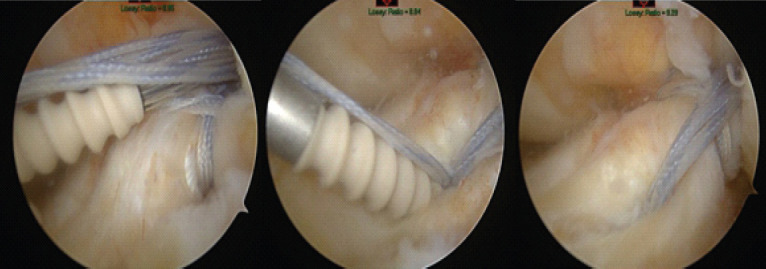

Case report: The authors present a case of a 60-year-old Caucasian female who developed a femoral-sided cyclops lesion after ACL repair. After initially achieving full range of motion (ROM) post-surgery, the patient later experienced a palpable clunk and extension loss 3-months postoperatively. While magnetic resonance imaging (MRI) was unremarkable, subsequent arthroscopy confirmed the diagnosis, leading to successful lesion excision and notchplasty.